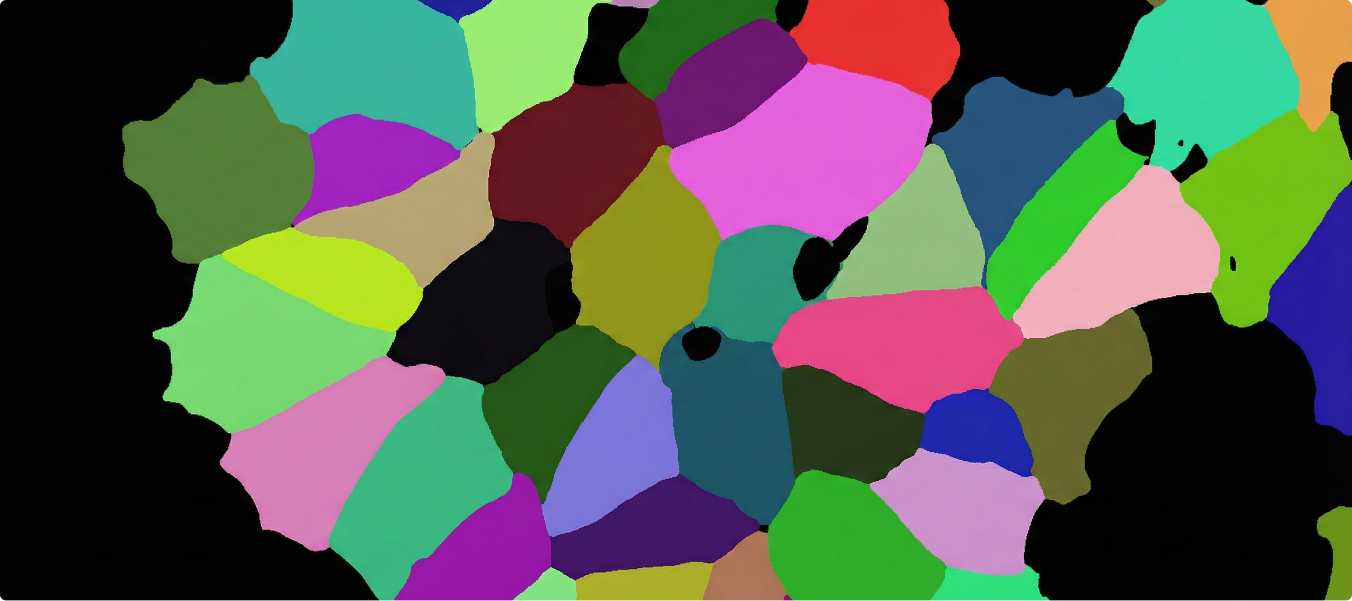

Microscopy images of Caliban cells required semantic segmentation, which is highly time-intensive. The challenge was handling extremely detailed data while maintaining accuracy.

• Applied semantic 2D annotation for detailed cellular segmentation.

• Ensured robust QC for consistency across large datasets.

• Supported biomedical research and AI model training.

• Completed annotations for 50k microscopy images of Caliban cells.

• Each annotation required about 1 hour per image, reflecting dataset complexity.

• Achieved 95% accuracy, ensuring precise cell segmentation.